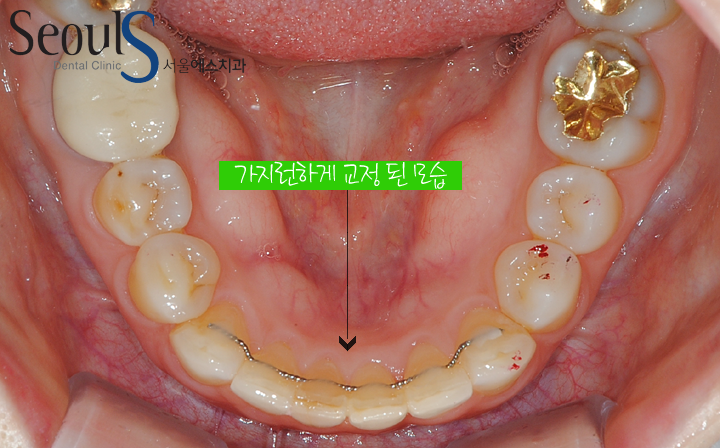

20170302-orth2 (7)

아랫니 교정 후 모습입니다

치아 사이를 다듬고 공간을 만들어 가지런하게 개선했습니다